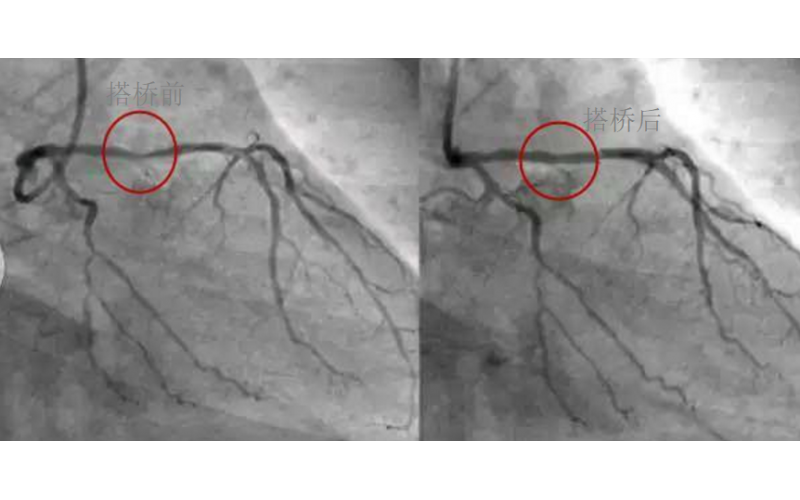

深圳市模具廠對心臟支架的關注,國產化的道路有多長?